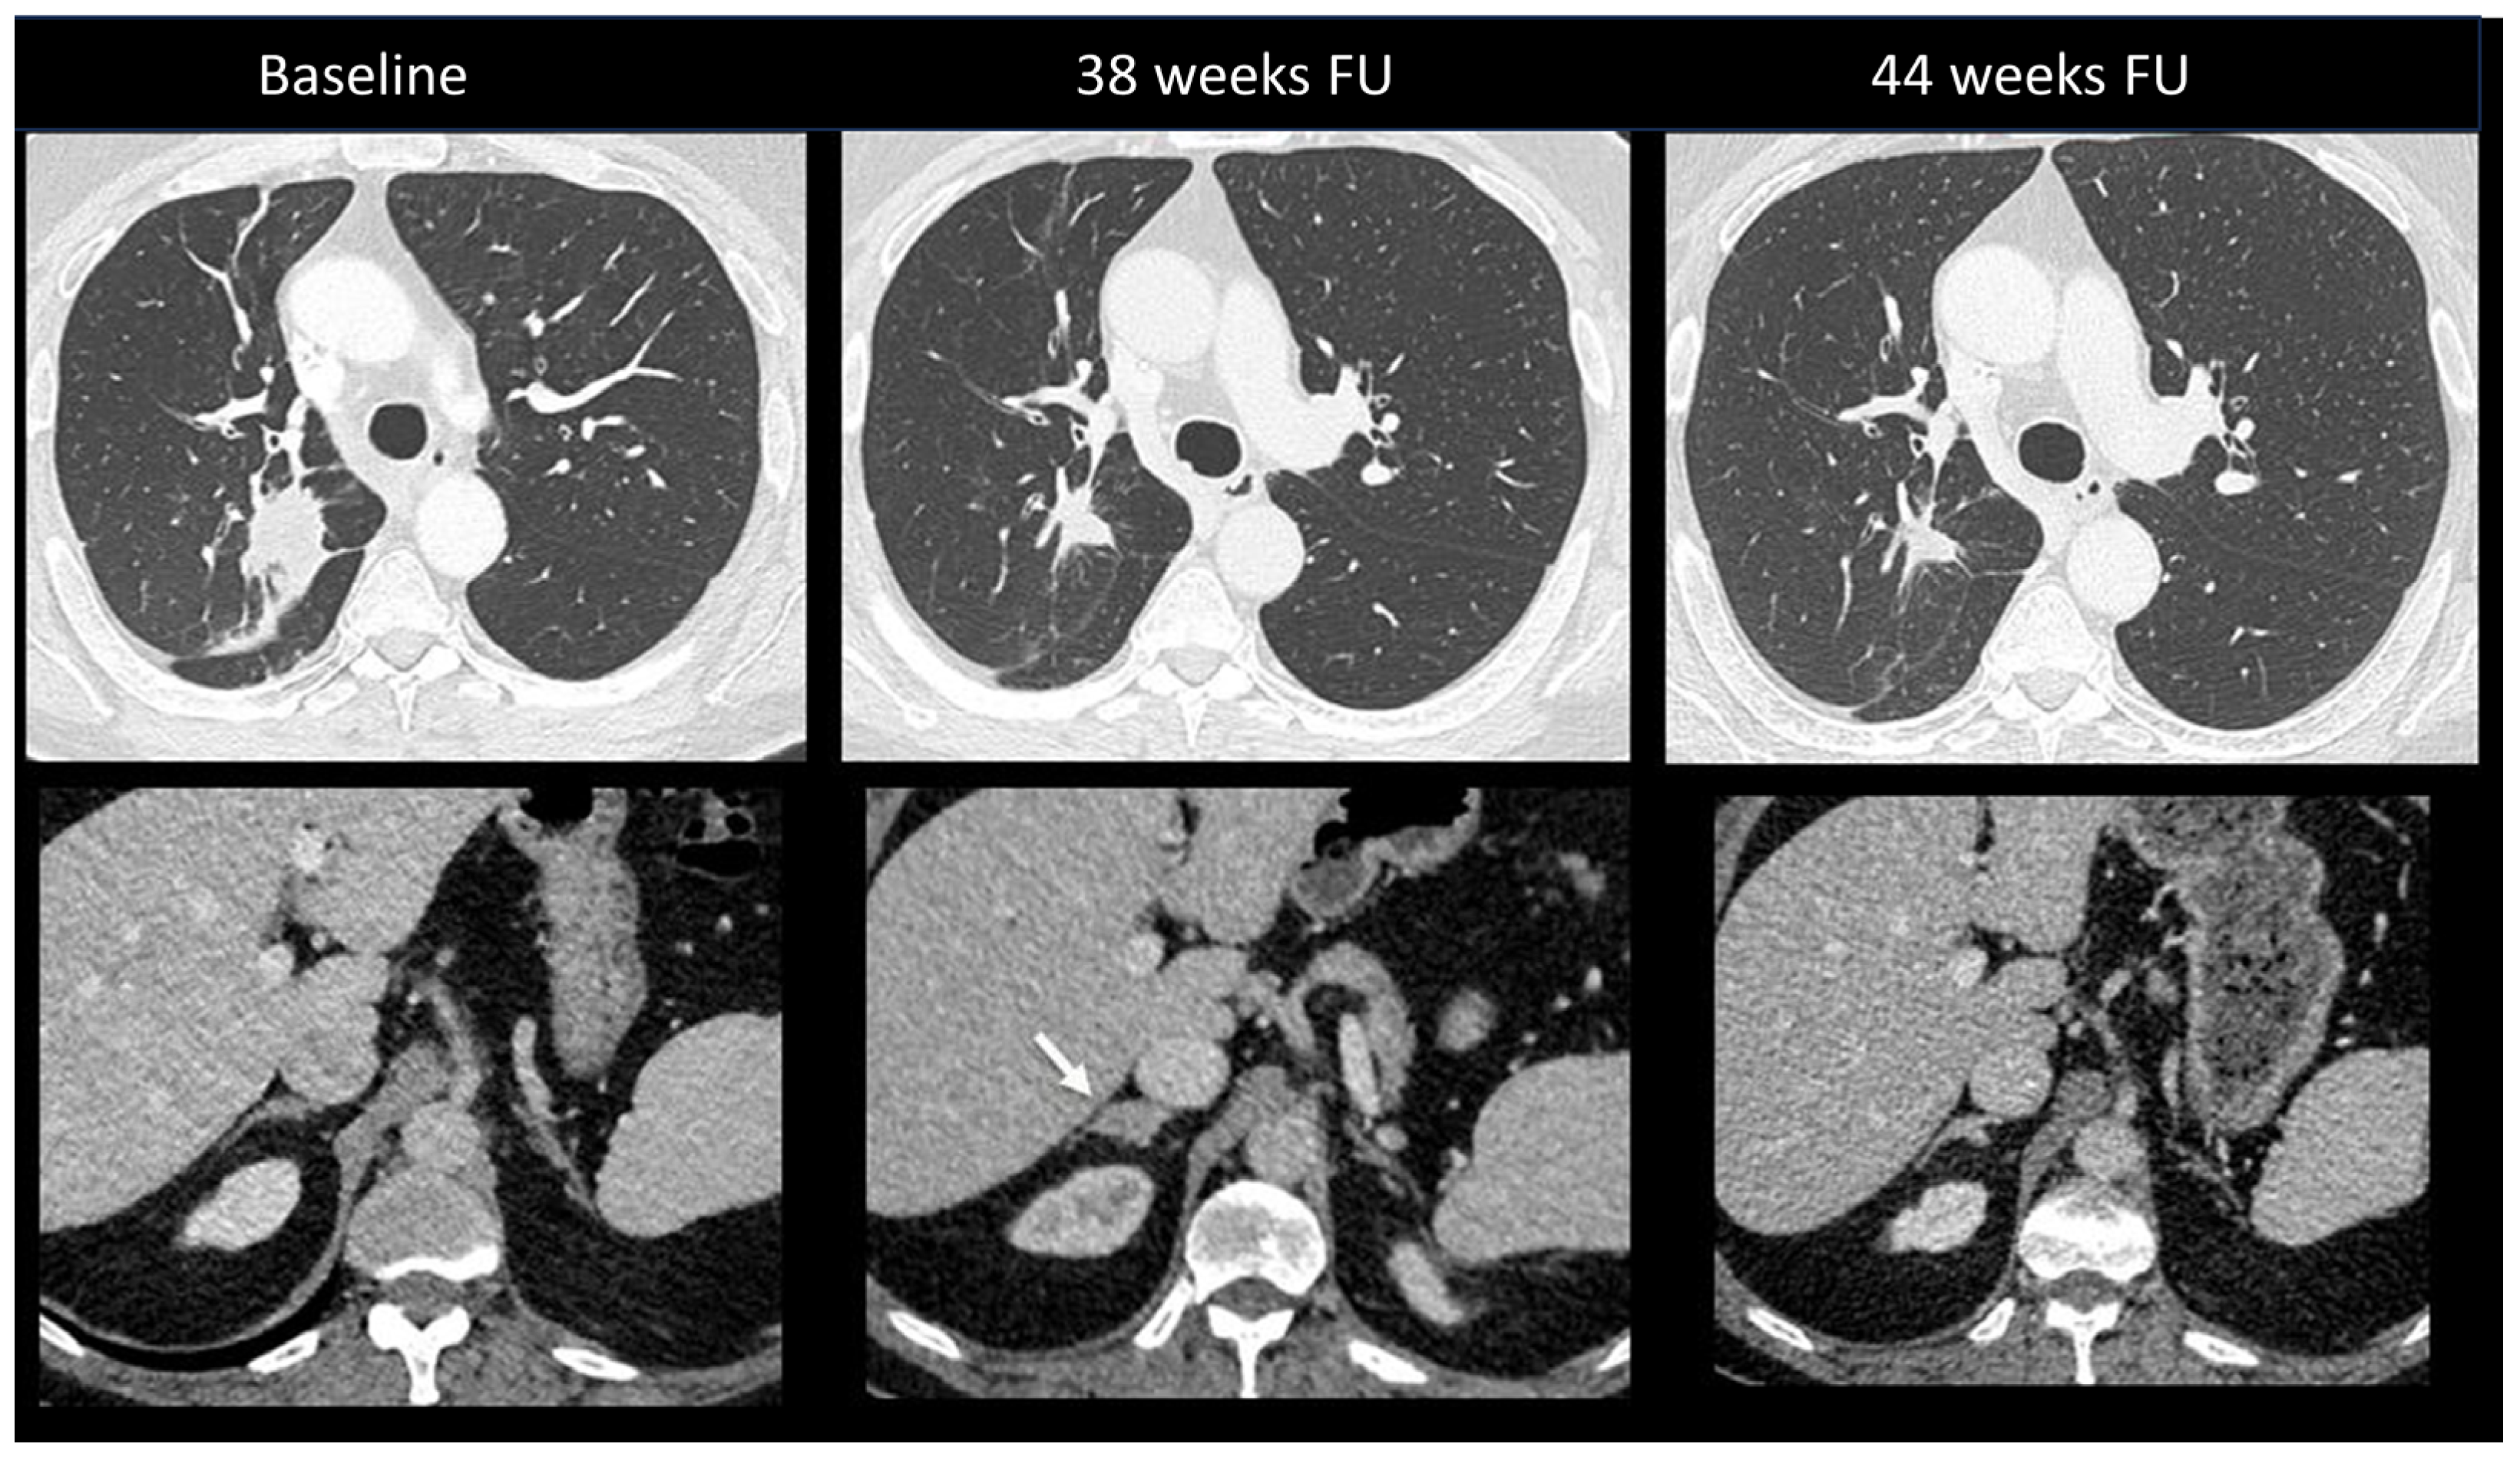

2.2.2. Sarcoidosis-Like Reaction

| Radiological Pattern | Main Radiological Findings | Main Radiological Clues and Tips | Main Differential Diagnosis | |

|---|---|---|---|---|

| Pneumonitis | OP | Multifocal, patchy, consolidations or GGOs with peribronchovascular and/or subpleural distribution | Migratory on a subsequent scan | Radiation Pneumonitis Infectious pneumonia Tumor progression |

| Other toxicities | Sarcoidosis-like Reaction | Enlarged hilar and mediastinal lymph nodes +/− bilateral perylimphatic (mainly scissural) micronodules | Bilateral and symmetrical | Lymph node metastasis disease Lymphangitis |